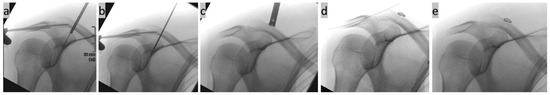

2. Surgical Technique